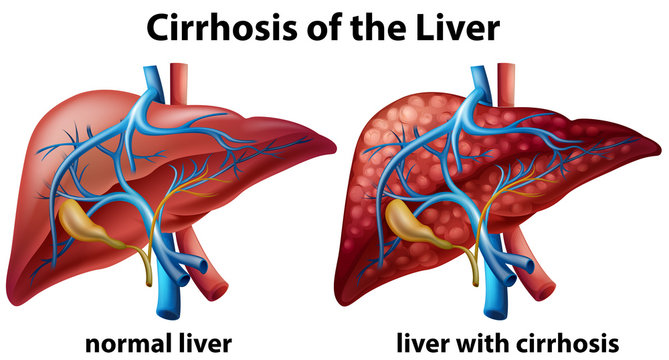

Cirrhosis Management

"Cirrhosis management is a comprehensive approach aimed at slowing disease progression and improving the quality of life. Lifestyle modifications, including a healthy diet, regular exercise, and alcohol abstinence, play a crucial role. Medications are prescribed to manage symptoms and complications such as fluid retention and nutritional deficiencies. Regular monitoring through liver function tests and imaging helps track disease progression, enabling timely interventions. Advanced cases may necessitate liver transplantation evaluation. Our expert team at [Your Clinic/Hospital Name] is dedicated to providing personalized cirrhosis management plans, emphasizing holistic care and ongoing support. Take the first step towards liver health today. #CirrhosisManagement #LiverHealth"